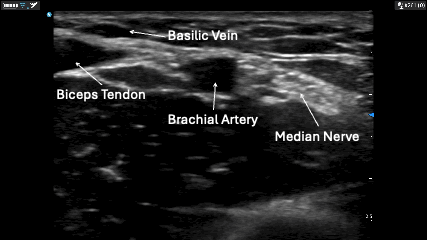

- The Brachial vein often runs closely parallel to the brachial artery and the median nerve. Proceed with caution and identify the adjacent structures before cannulation.